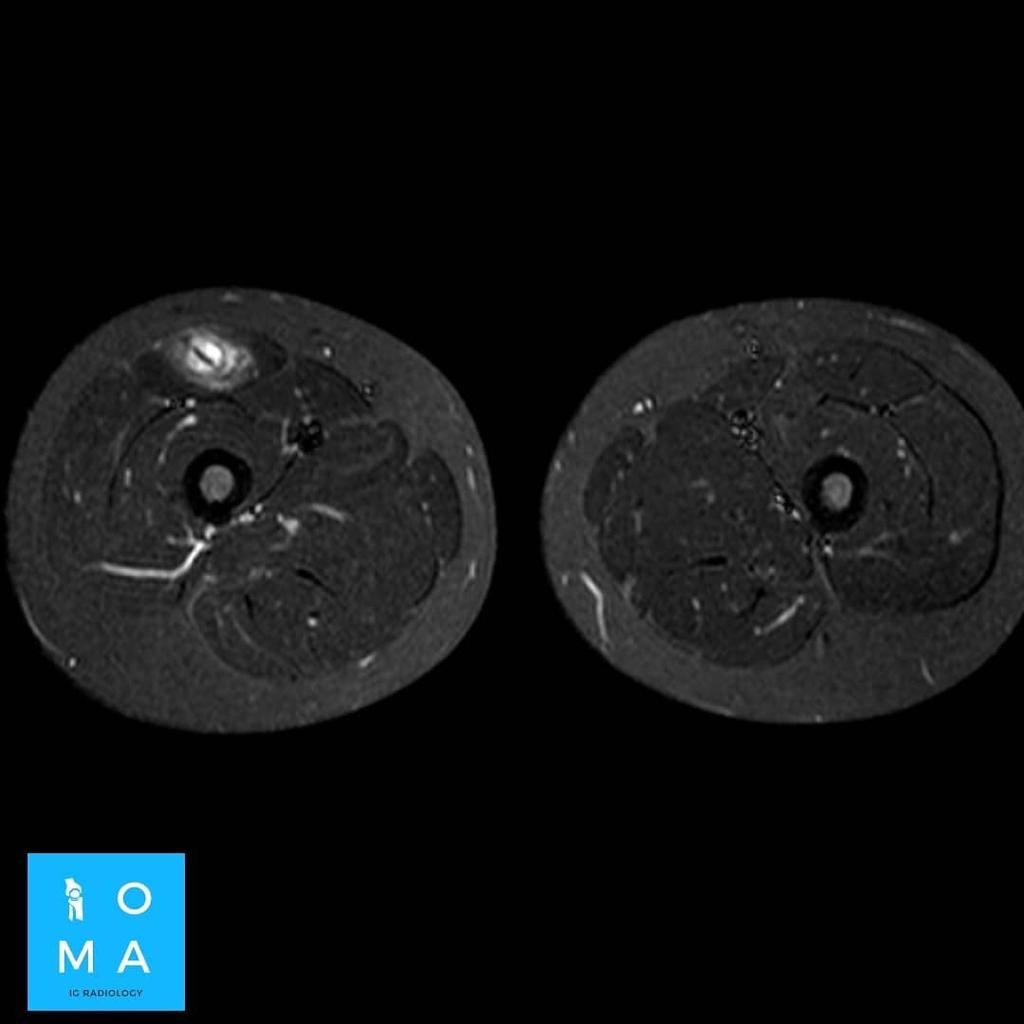

Desgarro fascicular del músculo glúteo mayor izquierdo. RM de tejido blando.

La RM es esencial para el diagnóstico de la topografía, severidad y extensión de los desgarros musculares. Un compromiso fibrilar mayor del 15% del área muscular con una longitud superior a los 13cm y una...